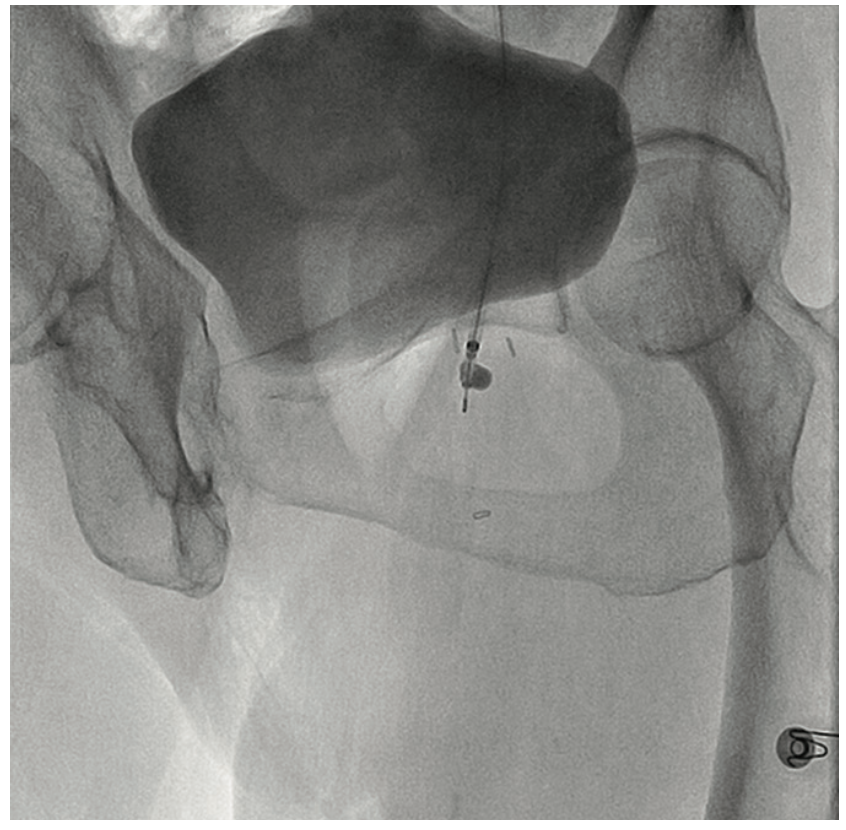

A 90-year-old woman presented with CLI of her left foot. She suffered from claudication beginning 12 years ago. Six months prior, she developed an ulcer on her foot and shortly thereafter, underwent femoral popliteal bypass. Her symptoms recurred and repeat fem-pop surgery was performed at that time. It immediately failed and she had a cadaveric vein placed as a fem-pop conduit, which again occluded and after two revisions of the fem-pop bypass, she was told five months prior to her current presentation that she would not be able to have any further intervention on her leg. At that time, it was suggested she go to hospice. A medial 1 cm x 6 cm foot ulcer was noted on examination, but the patient refused any intervention. Six weeks later, with insistence from the wound care center, and with the patient’s second and third digit now black on that foot, the patient permitted an evaluation for possible limb salvage. The examination showed that the foot was now cool and the second, third, and fourth digits were bluish-black. No pedal pulses were present. The patient was approached via the contralateral groin, and the angiogram revealed her native SFA and graft to be occluded at the origin (Figure 8). With the thought that there was a likelihood of thrombus in the vessel, we utilized the CrossLock LP and crossed the occlusion down to the tibial vessels with a Command wire (Abbott Vascular) wire (Figures 9-10). With some suggestion of thrombus in the digital arteries, 3 mg of tPA was administered locally. A .9 laser was used and subsequent balloon angioplasty was performed using embolic protection (Figures 11-12). The fluoroscopic time was 25.2 minutes and contrast was 273 cc. At the end of the procedure, the patient had 2-vessel infrapopliteal flow and several hours later, was seen by the orthopedic surgeon for metatarsal surgery. The surgeon stated that all the toes were now pink, the patient had palpable pedal pulses, and although it was very likely that some amount of amputation may be necessary in the second and third toe, nothing was removed, and the patient was discharged the next day.